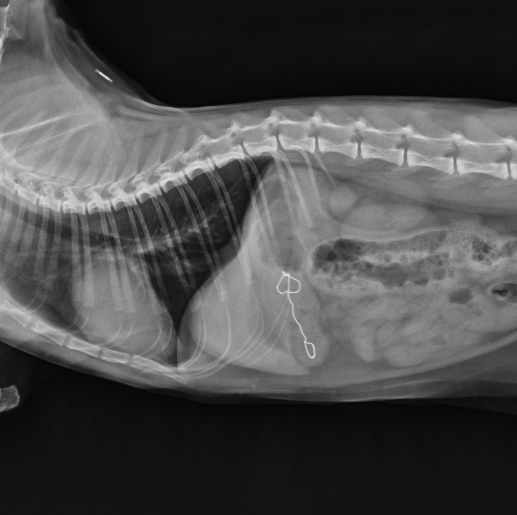

下の写真は当院で検査したX線検査での写真になります。